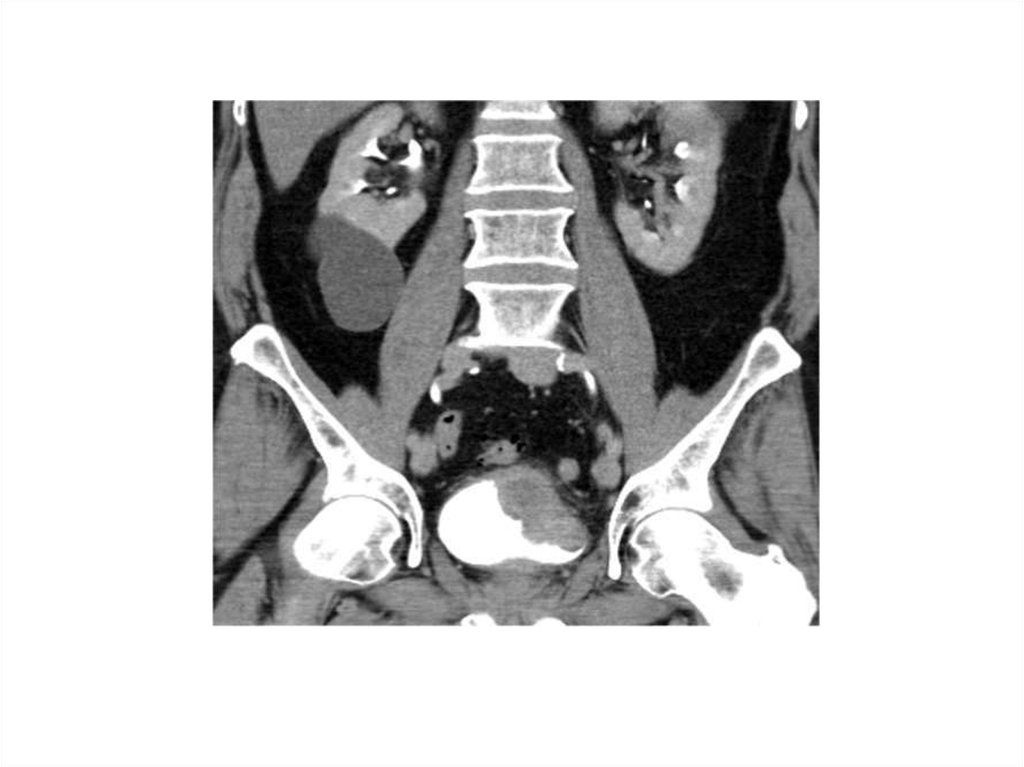

29. How is it Diagnosed?

Diagnostics

• Cystoscopy

• Tissue sample

• Radiologic Tests

• CT scan

• Stage & Grade